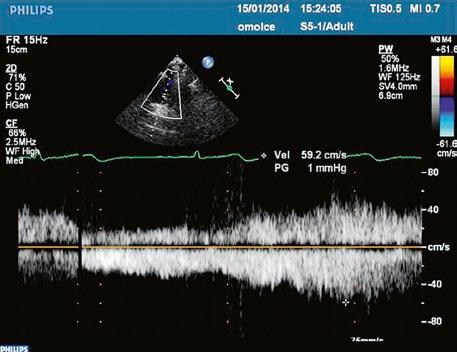

Malé restriktivní defekty komorového septa (Rogerova choroba) nevedou ke vzniku plicní hypertenze ani k srdečnímu selhání. Mají typickou vysokorychlostní dopplerovskou křivku (Obr. 45.35), odpovídající vysokém gradientu mezi levou a pravou komorou v systole a poslechovému nálezu hlučného systolického šelestu.

Obr. 45.35 CW záznam vysokorychlostního dopple rovského toku z levé do pravé komory malým restriktivním defektem komorového septa. Vysoký gradient na komorovém defektu vylučuje vysoký tlak v pravé komoře při plicní hypertenzi nebo při těžké stenóze plicnice.